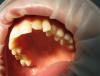

Уважаемые коллеги, ко мне пришла пациентка с жалобами на эстетику во фронтальной группе, слева.

Объективно:

1. транспозиция 2.3 и 2.2;

2. 2.2 дистопирован, кариозная полость на небной поверхности, подвижность в пределах физиологической;

3. скученность 1.2; 1.1; 2.1; 2.3; 2.2;

4. в боковых движениях: вправо- ведение клыковое, влево- ведение на 2.2.